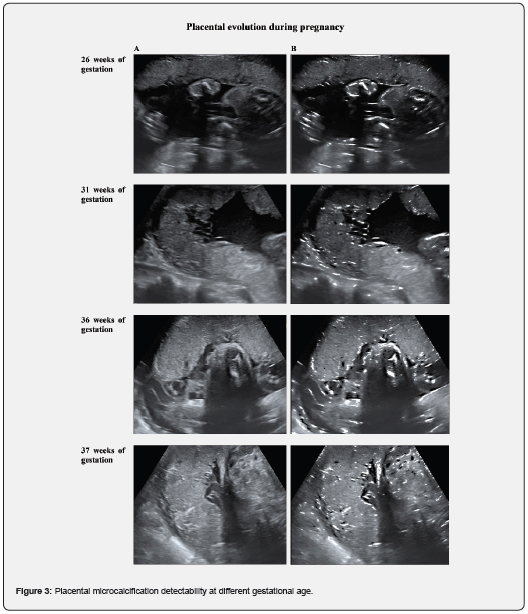

For the sake of visualization, we have chosen to present only zoomed visual results on a region containing microcalcifications. Figure 3 shows the influence of the filtering method in detectability of microcalcifications in the placenta for different weeks of gestation. We have observed the significantly enhanced visibility of less obvious microcalcifications (B) when compared to original ultrasound image (A).

Moreover, the image enhancement technique that we propose seems to be very reliable in the detection of preterm placental microcalcifications. One can notice that the proposed approach allows a better visibility of the small microcalcifications when these are difficult to identify in the original ultrasound images, especially before 32 weeks of gestation (figure 4 where A - original images containing microcalcification and B - corresponding images after improving details clarity).